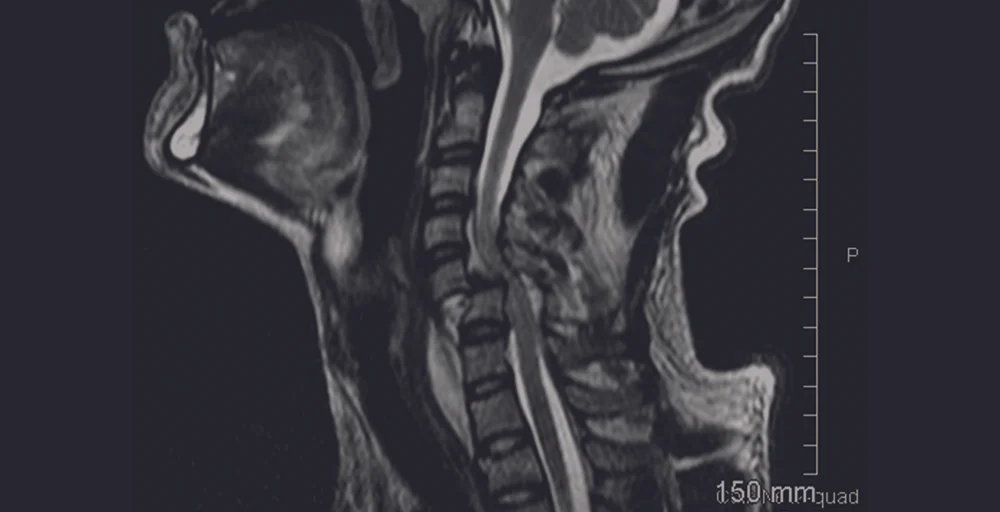

Paralysis is the loss of the ability to move (and sometimes to feel anything) in part or most of the body. While there are many causes of paralysis, one of the most common causes is when a person experiences a Spinal Cord Injury (SCI).

When a SCI occurs, there is usually swelling of the spinal cord. This may cause changes in virtually every system in the body. After days or weeks, the swelling begins to go down and people may regain some functioning. With many injuries, especially incomplete injuries, the individual may recover some functioning as late as 18 months after the injury. In very rare cases, people with SCI will regain some functioning years after the injury. Only a very small fraction of individuals sustaining SCIs recover all functioning.